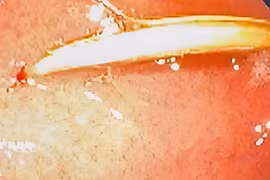

Cứu bé nuốt cây đinh vít, sơ cứu dị vật đường thở thế nào?

Các bác sĩ khoa Tai Mũi Họng đã nội soi đường thở cho bệnh nhân và gắp ra 1 chiếc đinh vít bằng sắt sắc nhọn từ phổi trái của bệnh nhân.